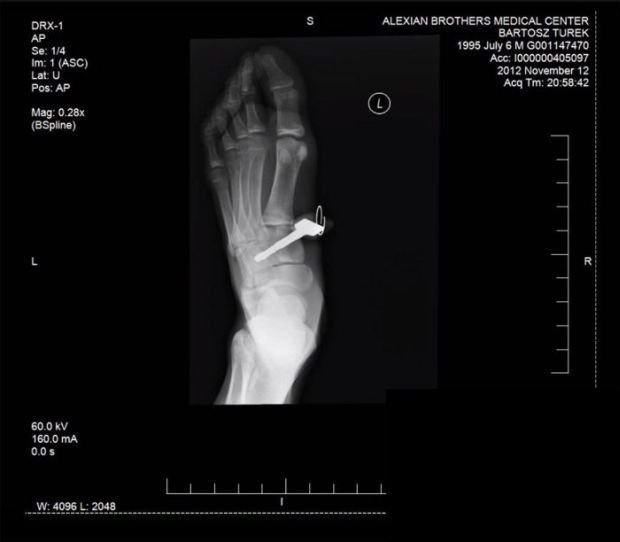

공수도(가라데)를 하다가 발바닥에 자동차 열쇠가 꽂히는 믿기 어려운 일이 일어나 누리꾼들을 놀라게 하고 있다.

공수도의 발차기가 얼마나 위력적이기에 이런 일이 가능할 수 있을까? 아니면 우연한 사고일까? 심약한 사람은 보지 말 것을 권한다. [사진출처 iage smource link]